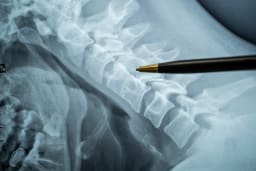

Ganglionektomie bei palmarem Handgelenkganglion

Im folgenden Beitrag werden alle wesentlichen Details einer Ganglionektomie bei palmarem Handgelenkganglion in Videosequenzen und Text dargestellt.